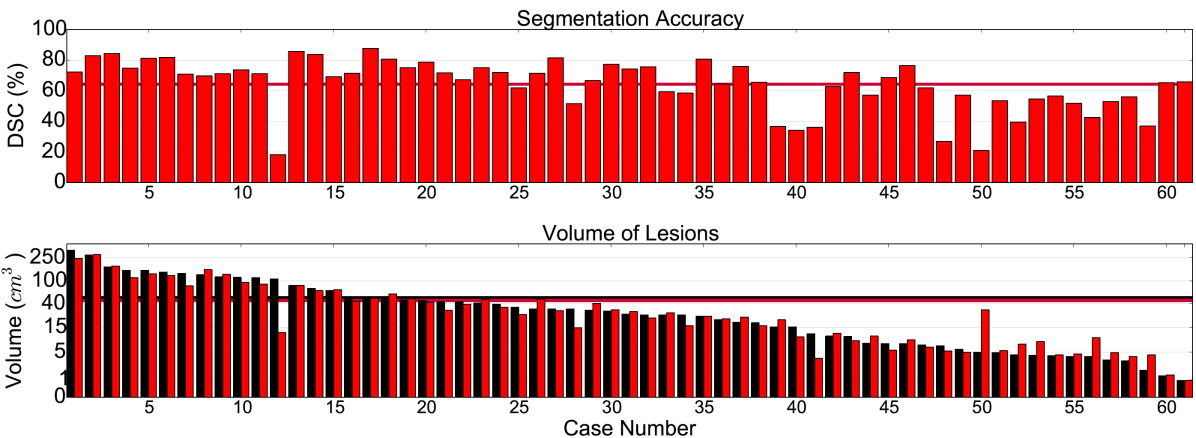

Table 1 summarizes the results on TBI. Our CNN significantly outperforms the Random Forest baseline, while the relatively overall low DSC values indicate the difficulty of the task. Due to randomness during training the local minima where a network converges are different between training sessions and some errors they produce differ (Choromanska et al. (2015)). To clear the unbiased errors of the network we form an ensemble of three similar networks, aggregating their output by averaging. This ensemble yields better performance in all metrics but also allows us to investigate the behaviour of our network focusing only on the biased errors. Fig. 10 shows the DSC obtained by the ensemble on each subject in relation to the manually segmented and predicted lesion volume. The network is capable of segmenting cases with very small lesions, although, performance is less robust in these cases as even small errors have large influence on the DSC metric. Investigation of the predicted lesion volume, which is an important biomarker for prognostication, shows that the network is neither biased towards the lesion nor background class, with promising results even on cases with very small lesions. Furthermore, we separately evaluate the influence of the post-processing with the fully connected CRF. As shown in Table 1, the CRF yields improvements over all classifiers. Effects are more prominent when the performance of the primary segmenter degrades, which shows the robustness of this regulariser. Fig. 11 shows three representative cases.